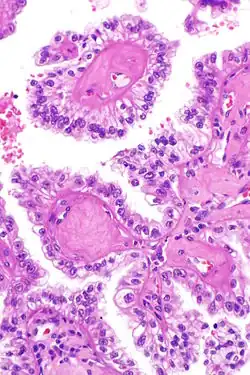

| Micrograph showing the characteristic hyalinized papillary cores found in some hereditary leiomyomatosis and renal cell carcinoma syndrome-associated renal cell carcinomas. H&E stain. | |

The renal cell carcinoma tends to be of the papillary (type 2) form and tends to occur more commonly in women than men with this syndrome. These cancers present earlier than is usual for renal cell carcinomas (typically in the twenties and thirties) and tend to be at relatively advanced stages at presentation. Tumours have rarely been reported in children. These tumours occur in ~20% of those with this mutation suggesting that other factors are involved in the pathogenesis.

The renal cell carcinomas have prominent eosinophilic nucleoli surrounded by a clear halo.